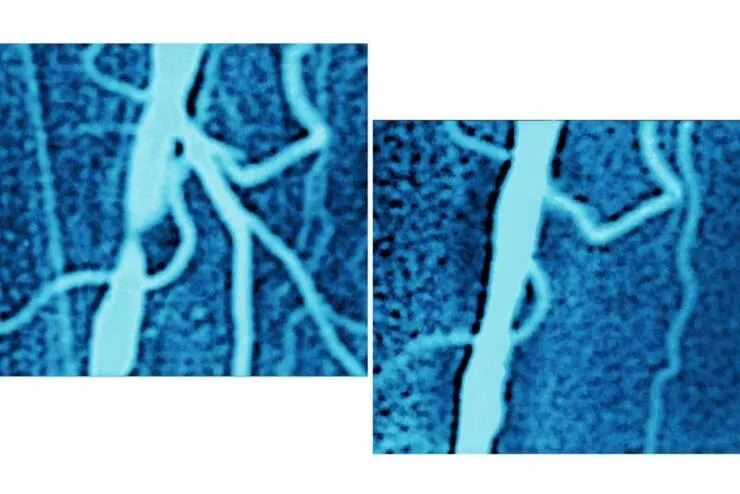

#25 Et l'artère iliaque d'un patient avant et après une procédure d'angioplastie :